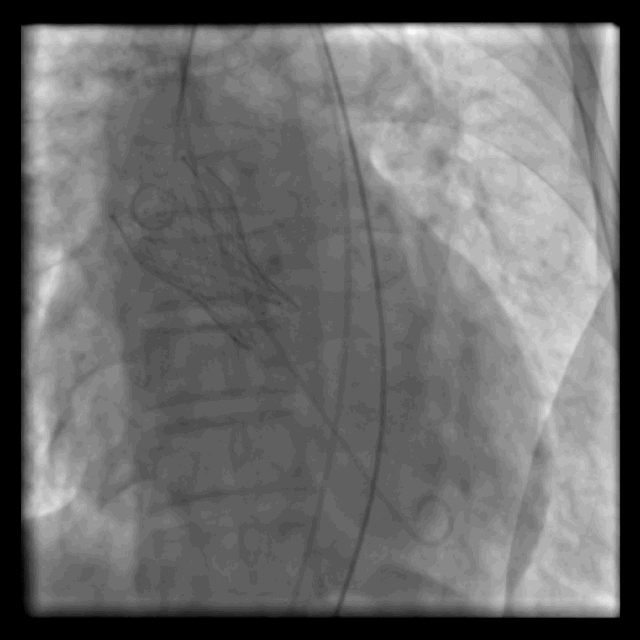

由于持续胸外按压下病人身体晃动及视野遮挡,术者沉着冷静,在短暂的按压间歇下成功完成导丝跨瓣,置换超硬导丝后送入23mm球囊,在无辅路造影、无起搏情况下成功进行球囊扩张。

扩张后患者为电机械分离状态,再次使用肾上腺素后患者心律部分恢复,频繁出现室速室颤,继续胸外按压、反复电除颤,同时建立辅路,快速将介入瓣膜导入主动脉根部,在按压间歇一次造影定位后即快速释放瓣膜。

释放瓣膜后患者心律恢复为窦性心律,血流动力学逐渐趋于平稳,再次造影无明显瓣周漏,跨瓣压差5mmHg,瓣膜位置理想。

心率恢复后造影